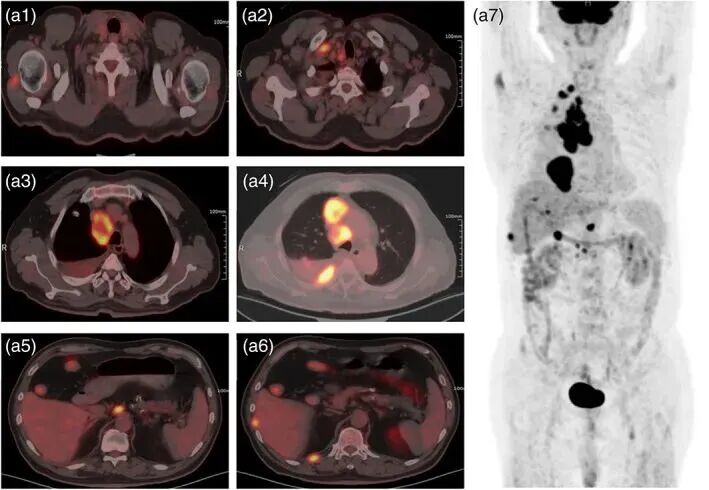

▲治疗前2022年5月拍摄的18F氟代脱氧葡萄糖正电子发射断层扫描/计算机断层扫描(18F-FDG PET/CT)图像

▲治疗5个月后,18F-脱氧葡萄糖正电子发射断层扫描/计算机断层扫描(18F-FDG PET-CT)图像的对比

令人震撼的是:三个月后,影像学复查显示,她肺部原本密布的亮点(结节及转移灶)大面积缩小甚至消退。医生团队在论文中写道,这一结果提示NK细胞有望在难治性肺癌患者中提供全新选择。